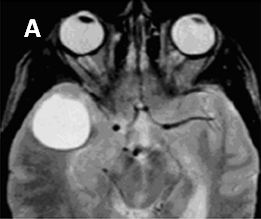

Hình 3. Hình ảnh di căn não đa ổ có lắng đọng canxi trên phim CT trước tiêm thuốc (A) và sau tiêm thuốc (B) của bệnh nhân ung thư dạ dày loại biểu mô tuyến chế nhầy có chảy máu trong u